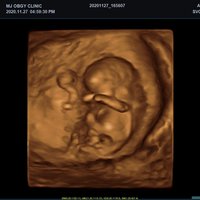

Volumen Konvex-Sonden

• SVC1-8H (1-8 MHz) für Ultraschalluntersuchungen in Bereichen Abdomen, Geburtshilfe, Gynäkologie, Urologie, Pädiatrie, EM